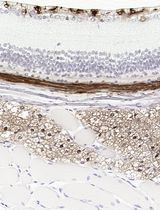

a. Flow cytometry: Detect cluster of differentiation (CD) markers on the cell surface. Use CD133 and CD44 as representative GBM markers (Figure 2A).

b. Immunofluorescent staining: Detect GBM-specific markers. Use Nestin and SOX2 as representative GBM markers (Figure 2B).